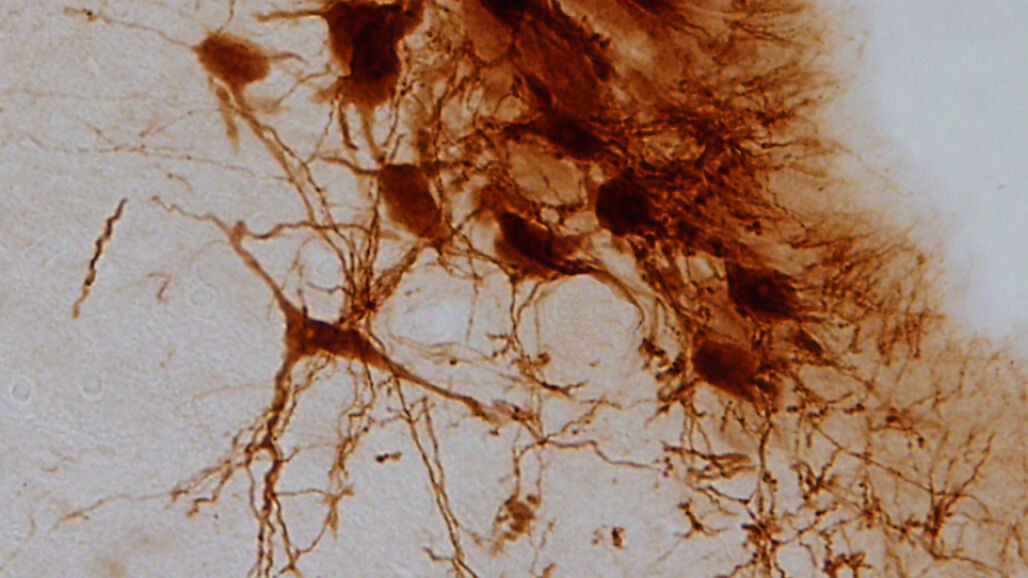

Sin embargo, este desarrollo se manifiesta en el cerebro mediante procesos diferentes. Cuando el dolor se origina por una diabetes mal controlada, este se refleja en el sistema nervioso central a través de una disminución en la producción de noradrenalina y una disfunción en la actividad del locus cerúleo, una región anatómica en el tallo cerebral involucrada en la respuesta al pánico y al estrés.

El locus cerúleo es el principal productor de noradrenalina del cerebro, una biomolécula involucrada en la transmisión del mensaje nervioso entre las neuronas y que desempeña un papel importante en la ansiedad y la depresión.